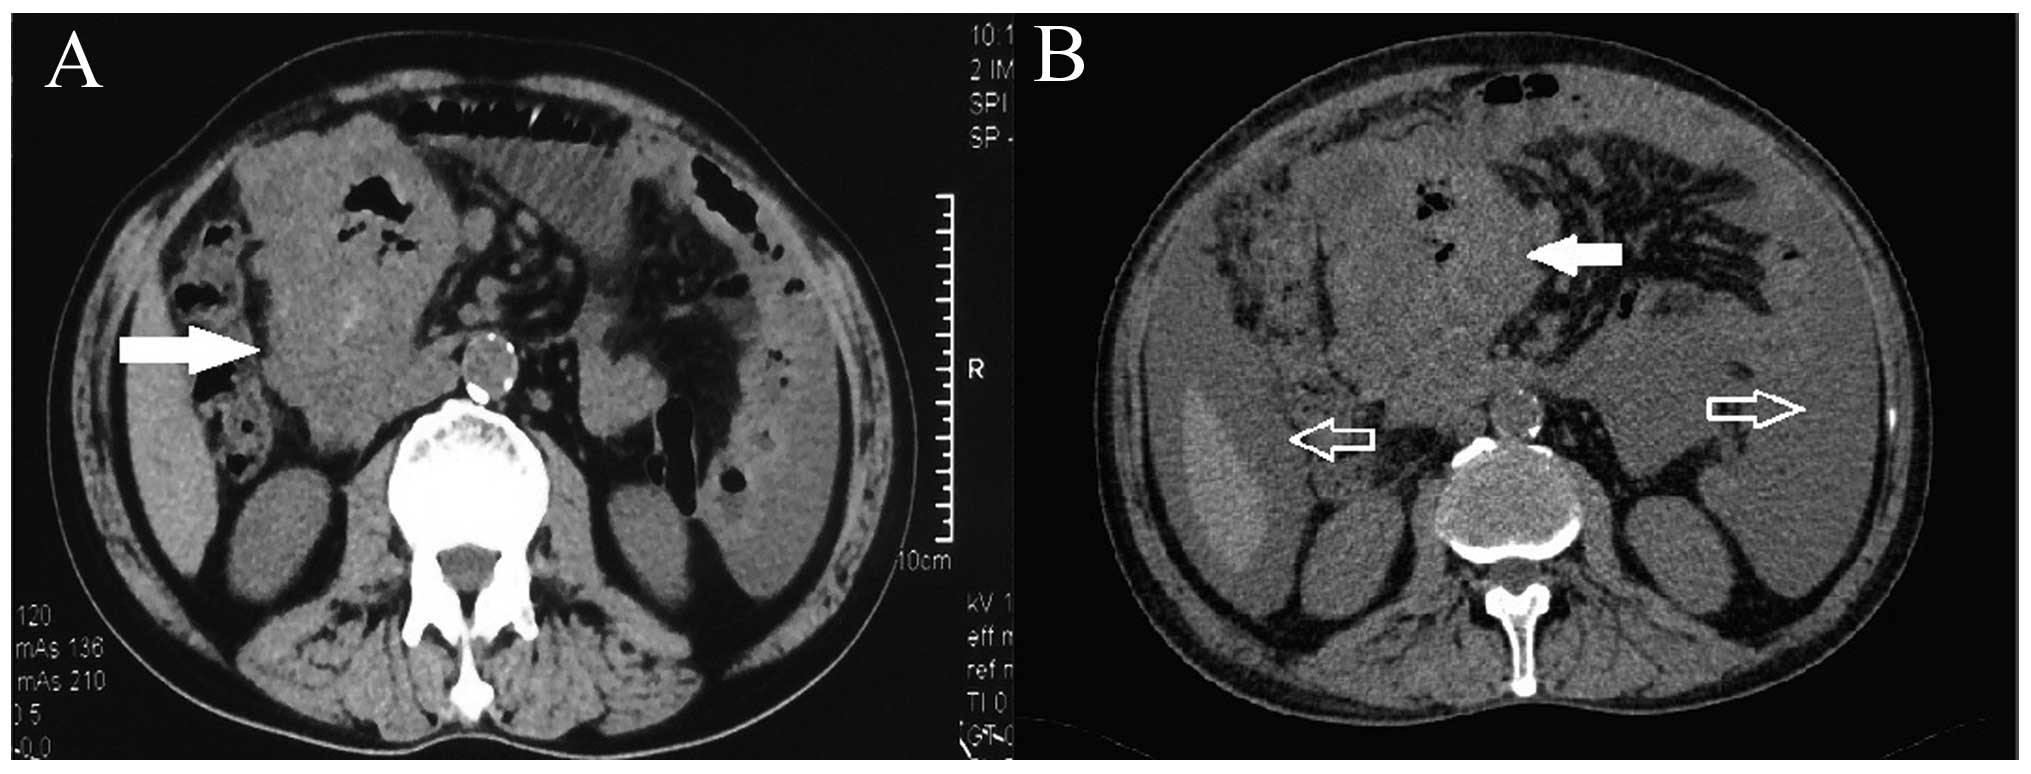

A 62-year-old man was admitted with complaints of intermittent abdominal pain and distension for 2 years. Two weeks prior to hospitalization, the patient suffered from continuous abdominal distension and he developed new symptoms including melaena, dizziness and fatigue. There had been no recent change in bowel habits. The patient was diagnosed with severe anaemia and hypoproteinemia at a local hospital, but his symptoms were not alleviated following conservative treatment and blood transfusion. An abdominal computed tomography (CT) scan revealed a bulky mass, sized 11×6.5×4 cm3, possibly originating from the small intestine (Fig. 1A). The patient was then admitted to our hospital for further investigation and treatment.

Following medication therapy and blood transfusion for 24 h, the patient complained of progressive aggravation of the abdominal distension, palpitations and shortness of breath on effort. Notably, the blood test results for Hb (4.9 g/dl), Hct (16%) and RBC count (1.72×1012/l) were prominently decreased. In addition to the primary tumor, massive ascites was also observed on CT re-examination (Fig. 1B). Additionally, abdominal paracentesis revealed the presence of free blood in the peritoneal cavity. The patient underwent emergency explorative laparotomy, as there was a high possibility of cancerous and gastrointestinal bleeding, as well as other complications.